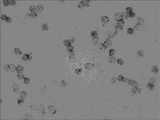

Fig. 3 is high risk population's picture in the embodiment of the invention.

20 of hepatocarcinoma patients, 20 of high risk population's (hbv-liver cirrhosis), 20 of normal control groups.Take out all people's to be checked peripheral blood 3-5 milliliter (separation white corpuscle) and do in situ hybridization.The result representes that all cancer patients MICRORNA-21 expression amounts are high, and cell dyeing is dark; The high risk population expresses slightly and reduces, decimal dyeing; Normal control group MICRORNA-21 expression amount is low, the dyeing of cell minority, and concrete outcome is seen Fig. 2, Fig. 3, Fig. 4.